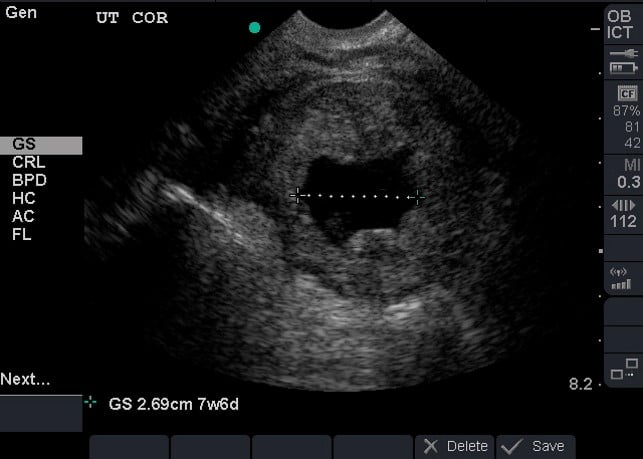

- Dating can be achieved by obtaining crown rump length when fetal pole becomes visible and then biparietal diameter when fetal skull becomes evident at the end of the first trimester.1 (Illustration 10, 11)

- Illustration 10. Transabdominal transverse view of 10-week fetus with crown rump length measurement.